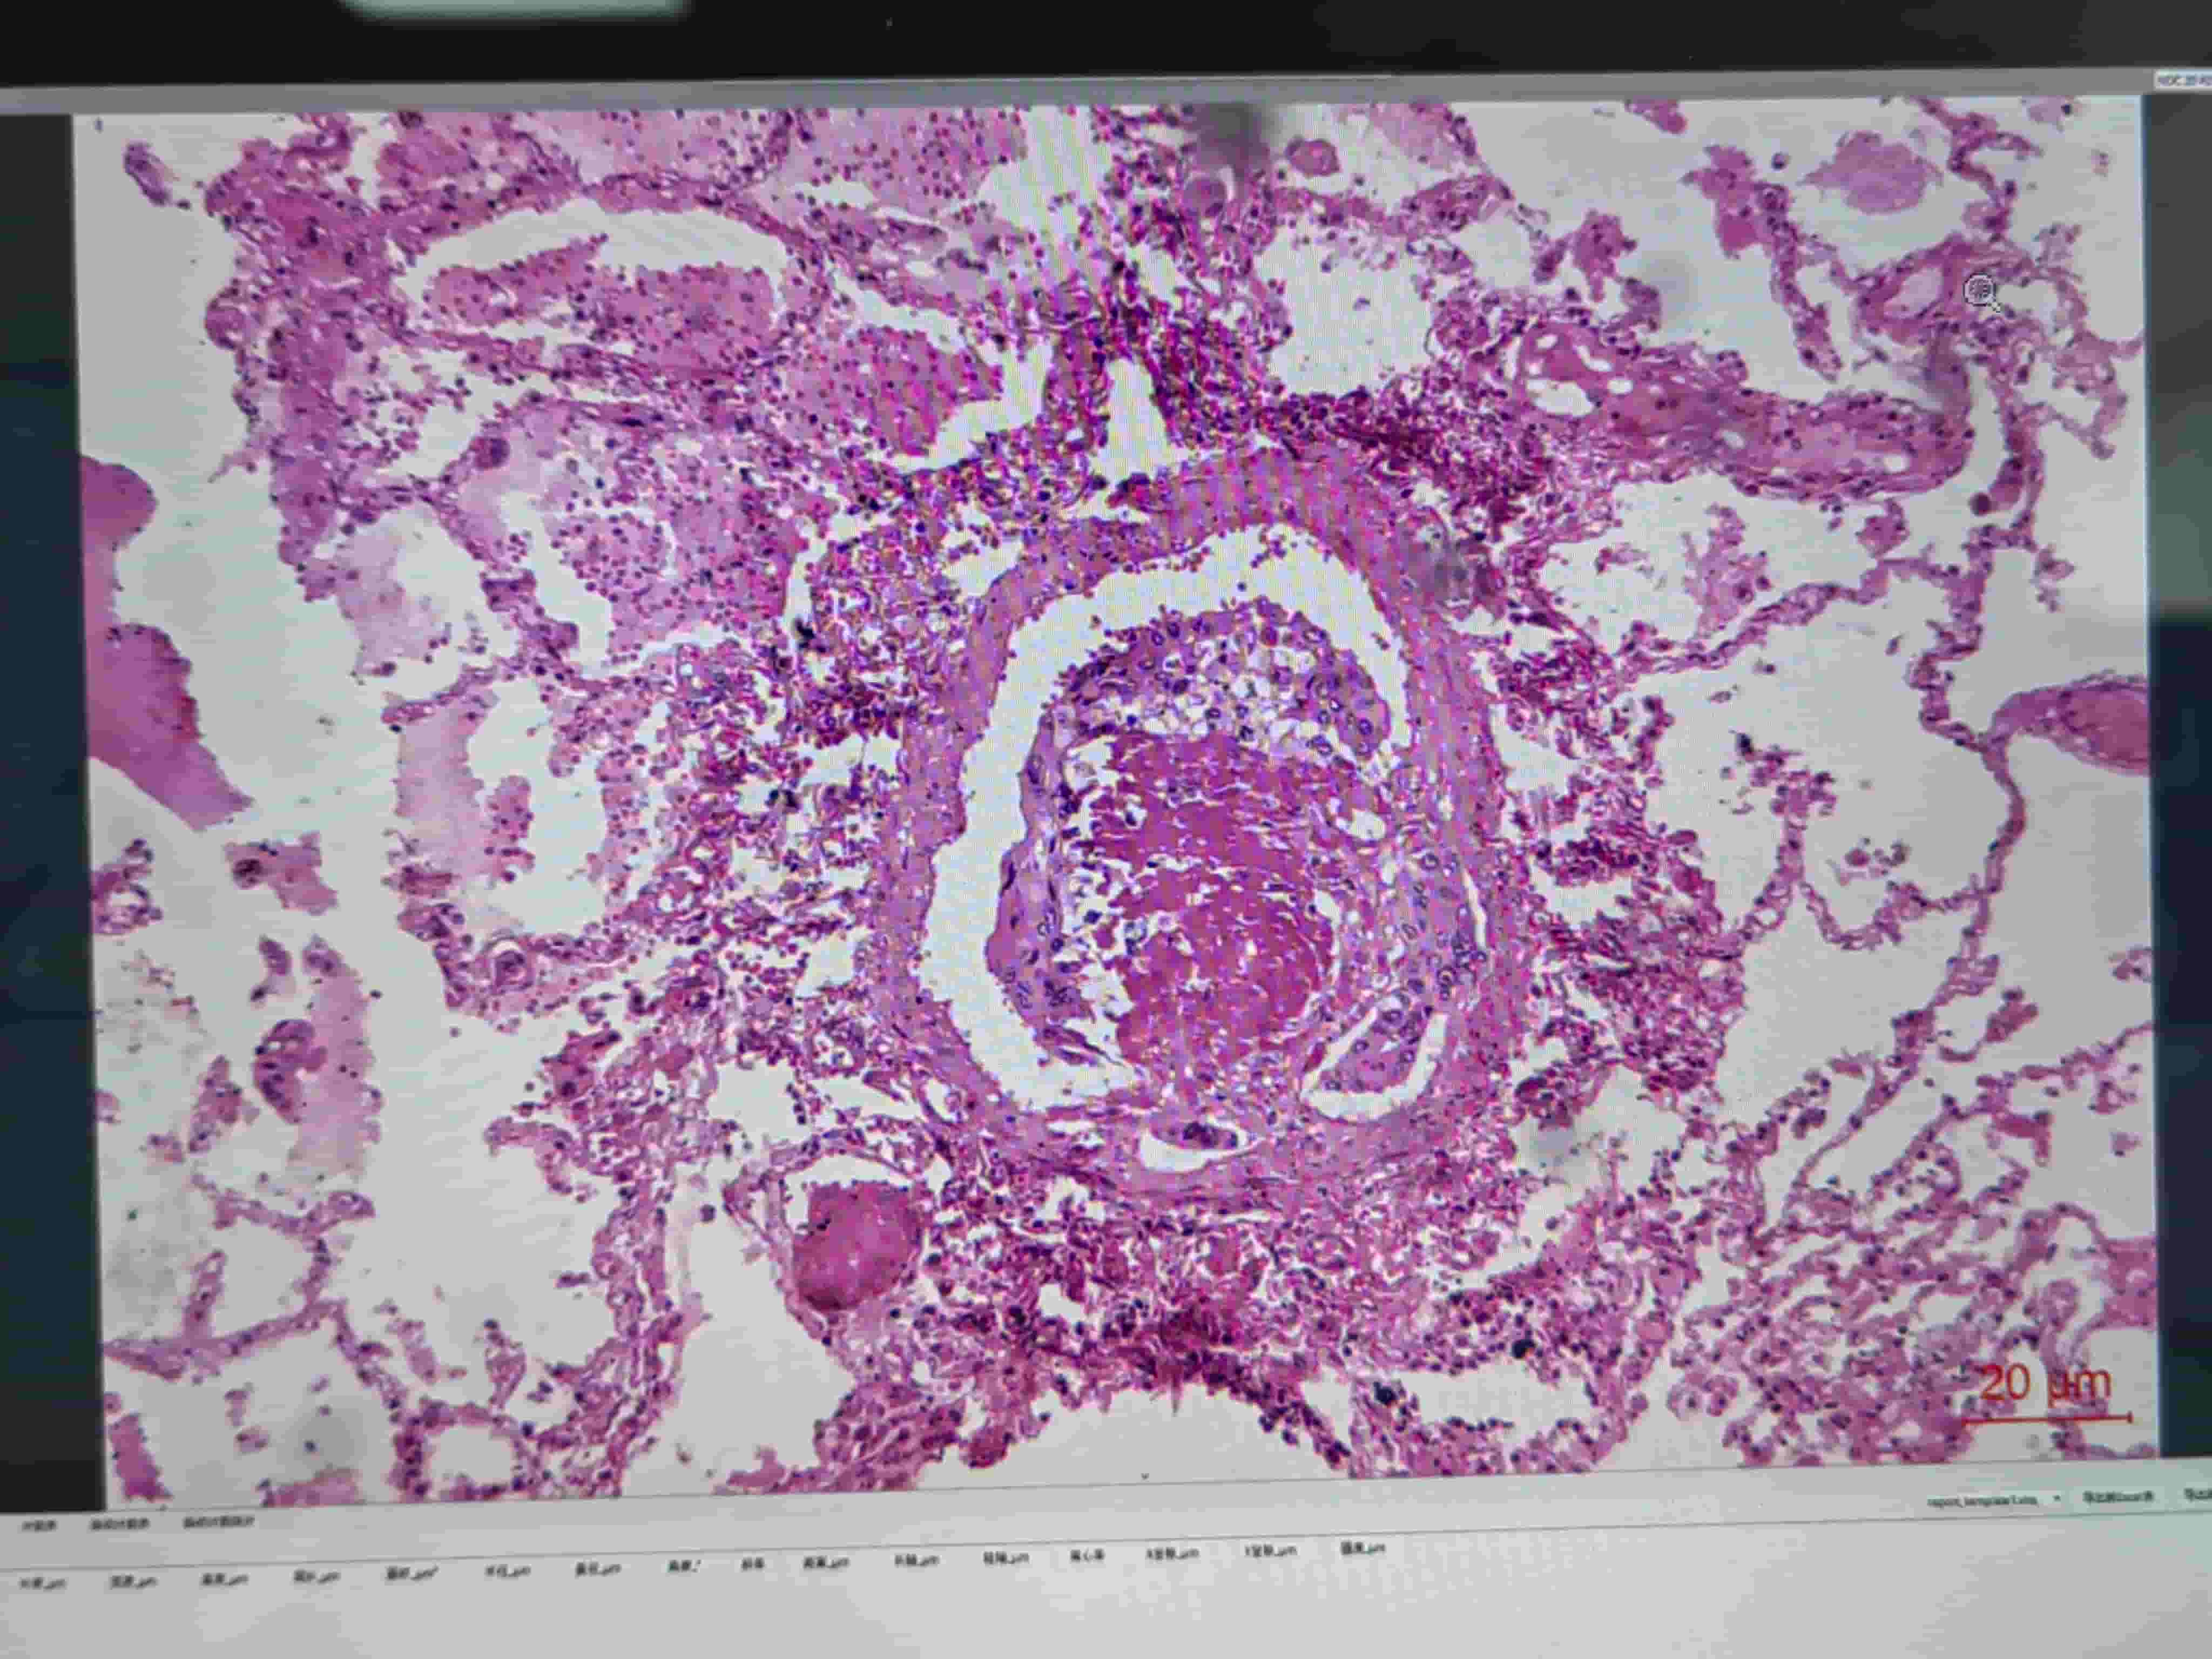

硅肺.0.0

硅肺.0.1

硅肺.0

硅肺.1

硅肺.2

硅肺